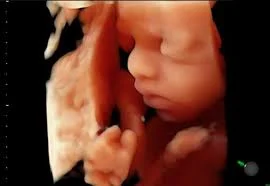

Imagens 3D e 5D

Permitem que você viva a experiência de acompanhar os movimentos e o desenvolvimento do bebê em tempo real, como seus gestos, expressões e características físicas, criando memórias inestimáveis.